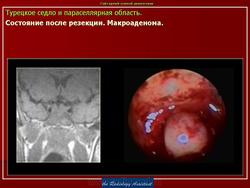

ГМ. Аденома гипофиза 1. +

Аденома гипофиза.